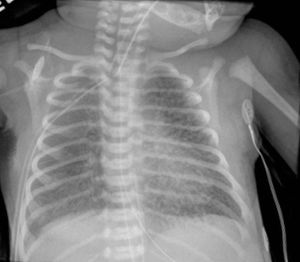

신생아 호흡곤란 증후군은 미국에서 모든 출생의 약 1%에서 출생 후 6시간 이내에 가장 흔하게 발생한다.[18] 주요 위험 요인은 미숙아이며, 750g 미만의 영아에서 발생 가능성은 최대 71%까지 증가한다.[19] 다른 위험 요인으로는 당뇨병 산모의 영아(IDM), 분만 방법, 태아 질식, 유전학, 막의 장기 파열(PROM), 임신 중독증, 융모 양막염, 남성 성별이 있다. 호흡곤란 증후군의 널리 받아들여지는 병태생리는 불충분한 폐활량소 생성과 미숙한 폐 및 혈관 발달로 인해 발생한다는 것이다. 폐활량소 부족으로 인해 폐가 무기폐가 되어 환기/관류 불일치, 감소된 폐순응도 및 증가된 기도 저항이 발생한다. 이로 인해 저산소증과 호흡성 산증이 발생하여 폐 고혈압으로 이어질 수 있다. X선 사진에서 ground glass appearance(모래알 유리 모양)을 보인다. 증상으로는 빈호흡, 비강 확장, 역설적 흉부 운동, 그렁거림 및 늑골 하부 함몰이 포함될 수 있다.[18]